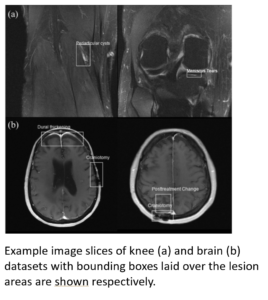

This work introduces fastMRI+ (opens in new tab), which consists of 16154 subspecialist expert bounding box annotations and 13 study-level labels for 22 different pathology categories on the fastMRI knee dataset, and 7570 subspecialist expert bounding box annotations and 643 study-level labels for 30 different pathology categories for the fastMRI brain dataset.

Example Images with Annonations